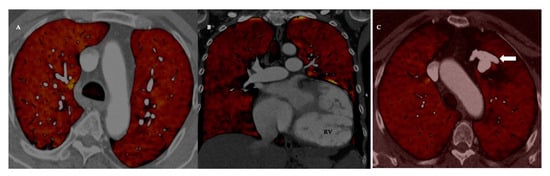

3.2. Dual Energy CT, DECT